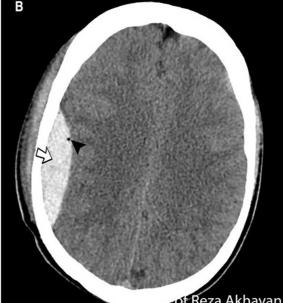

4

5

Perfectly

8